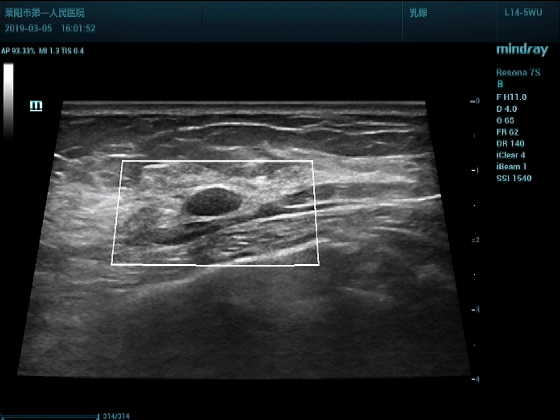

超声入门贴994--乳腺纤维瘤(弹性成像)